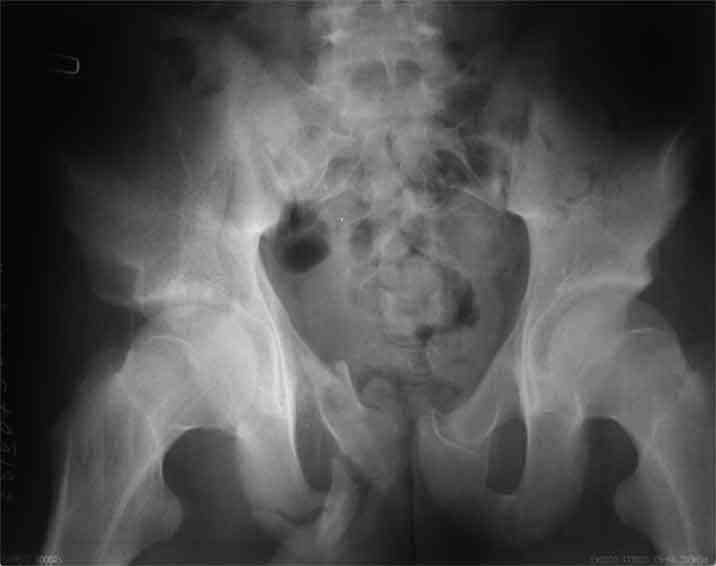

Не смог разглядеть на представленных картинках частичное повреждение левого КП, повреждение Денис1-2 справа? 3Д реконструкции в инлет и боковой проекциях убедительно не демонстрируют типа повреждения задних отделов тазового кольца(справа боковая масса скомпремирована), Наверное, у тебя есть возможность оценить тип перелома крестца по прямой проекции 3Д.

По вертлуге- смог разглядеть только изолированный перелом передней колонны.

Насколько я понял из твоего письма, обращенного к анонимному vit, ты не видишь показаний к реконструкции перелома. Я бы взялся за реконструкцию(илео-ингвинальный доступ), хоть прошел и месяц после травмы: боковая 3Д показывает смещение нагрузочной зоны впадины, что однозначно будет способствовать разрушению хряща головки и впадины( особенно у 16 летнего пациента с ожидаемым высоким уровнем активности) + изменение геометрии впадины за счет неустраненного смещения фрагментов колонны (КТ, 3Д данные).

На мой взгляд, без реконструкции этот сустав обречен (концепция вторичной конгруэтности в данных условиях работать не будет), реконструкция дает шанс на восстановление функции сустава.

В данном случае 3D и корональные срезы КТ менее информативны, чем поперечные. Согласен с левосторенним минимальным повреждением КПС, но не смог уловить перелом крестца.

По представленным материалам, мне кажется, перелом был передней колонны ацетабулум с минимальным вовлечением нагрузочной поверхности сустава, левосторенний повреждение КПС и лонных костей.

При свежем случае показана фиксация передней колонны к задней (снимки), компрессирующим винтом минимальным перкутанным методом по супраацетабулярной линии и в зависимости от состояния КПС.

Поэтому, в ранних и в спорных сомнительных случаях полезно проведение EUA (evaluation under anesthesia) в условиях операционной с доказательными нагрузочными рентгеновскими снимками. В данном случае, учитывая молодой возраст и прошедшее время, я бы оставил больного для дальнейшего консервативного наблюдения.

Стандартные снимки ацетабулума по Judet и снимки таза (инлет и оутлет) подскажут дальнейшую тактику по нагрузке.